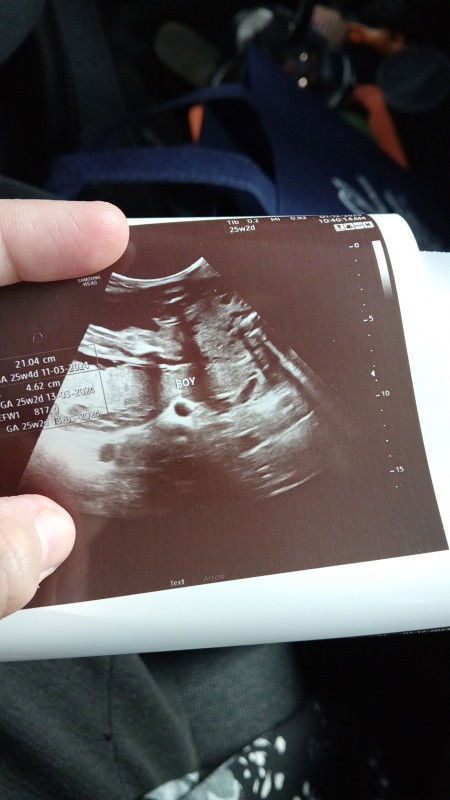

Pinjam mata burung baby yg mana satu. Jenuh pusing2 gambar🤣

#gender #25weeks #baby

dari sisi bawah kot ni. bulat tu la macam testicle dia